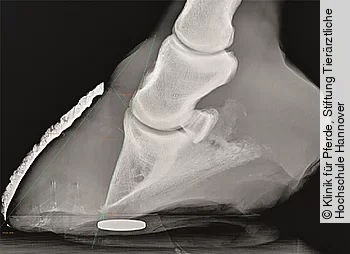

Pferde mit EMS leiden immer an einer Insulindysregulation. Zu berücksichtigen ist allerdings, dass auch Pferde und Ponies, die auf den ersten Blick keine Anzeichen einer Adipositas aufweisen, an einer ID leiden können. Sie können somit für eine endokrinopathisch bedingte Hufrehe prädisponiert sein (Abb. 1). Umgekehrt muss nicht jedes adipöse Pferd unter einem EMS und demzufolge an einer ID leiden.

Pferde, die an einer ID leiden, haben ein besonders hohes Risiko, eine endokrinopathische Hufrehe zu entwickeln (Abb. 3). Studien zeigen, dass 70–89% aller Pferde mit Hufrehe an einer Endokrinopathie leiden. Ungefähr ⅓ aller Pferde mit einer Endokrinopathie hatte eine PPID und bei ⅔ aller Pferde mit Hufrehe zeigte sich labordiagnostisch eine Hyperinsulinämie und dementsprechend der Hinweis auf eine ID. Es wird angenommen, dass die Hyperinsulinämie ein wichtiger Hufrehe-auslösender Faktor der endokrin bedingten Erkrankungen EMS und PPID ist. Selbst bei gesunden Pferden und Ponies lässt ich durch eine experimentell induzierte Hyperinsulinämie eine klinisch manifeste Hufrehe auslösen. Bei Ponies mit ID konnte zudem durch eine Fütterung einer hochdosierten Kohlenhydratration über mehrere Tage und einer daraus resultierenden hochgradigen postprandialen Hyperinsulinämie eine ebenfalls klinisch manifeste Hufrehe ausgelöst werden.